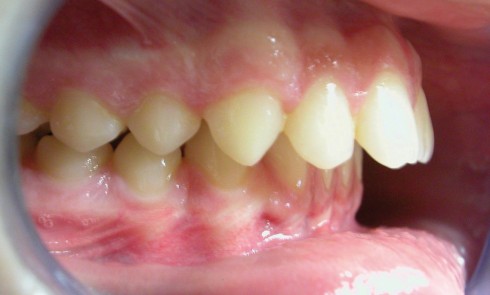

Article réservé à nos abonnés Traitement d’une classe II associant multibagues et Optimax Fix

Présentation Il s’agit d’un patient âgé de 13 ans qui présente une classe II-2 supraclusie associée à un encombrement mineur...